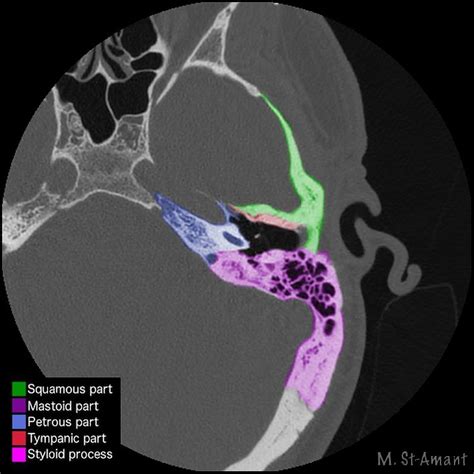

• The squamous part: This is the largest and most superficial part, forming the side of the skull.

• The petrous part: This dense, pyramid-shaped portion houses the inner ear structures, including the cochlea and vestibular system.

• The mastoid part: Located behind the ear, it contains air cells and the mastoid antrum.

• The tympanic part: This ring-shaped structure forms the bony part of the external ear canal.

The Ct Temporal Bone scan is particularly useful in visualizing these intricate structures due to its high-resolution imaging capabilities. This makes it an invaluable tool for diagnosing various conditions affecting the temporal bone.